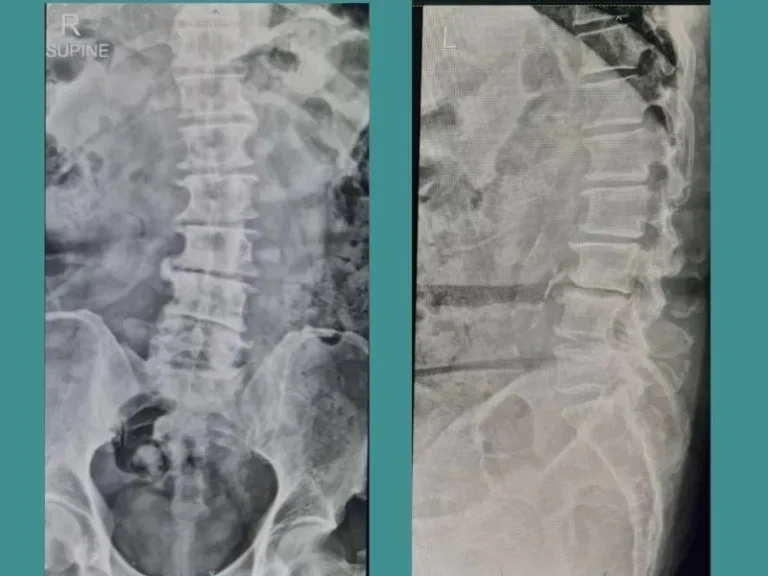

เมิ่อมีการเข้าตรวจประเมินอาการปวดหลัง หรือ ปวดคอ และพบว่ามีอาการบ่งชี้ของกระดูกสันหลังเคลื่อน หมอนรองกระดูกปลิ้น...

อาการดังกล่าวไม่ใช่อาการปวดจาก โรคหมอนรองกระดูกกดเบียดเส้นประสาทแต่อย่างใด...

หมอนรองกระดูก“เสื่อม” เกิดจากสาเหตุหลักๆคือ1.เกิดจากใช้งานในชีวิตประจำวัน2.อายุที่มากขึ้น

ปัจจุบันพบในผู้ป่วยอายุที่น้อยมากขึ้นเนื่องจากการใช้ชีวิตประจำวันและพฤติกรรม...